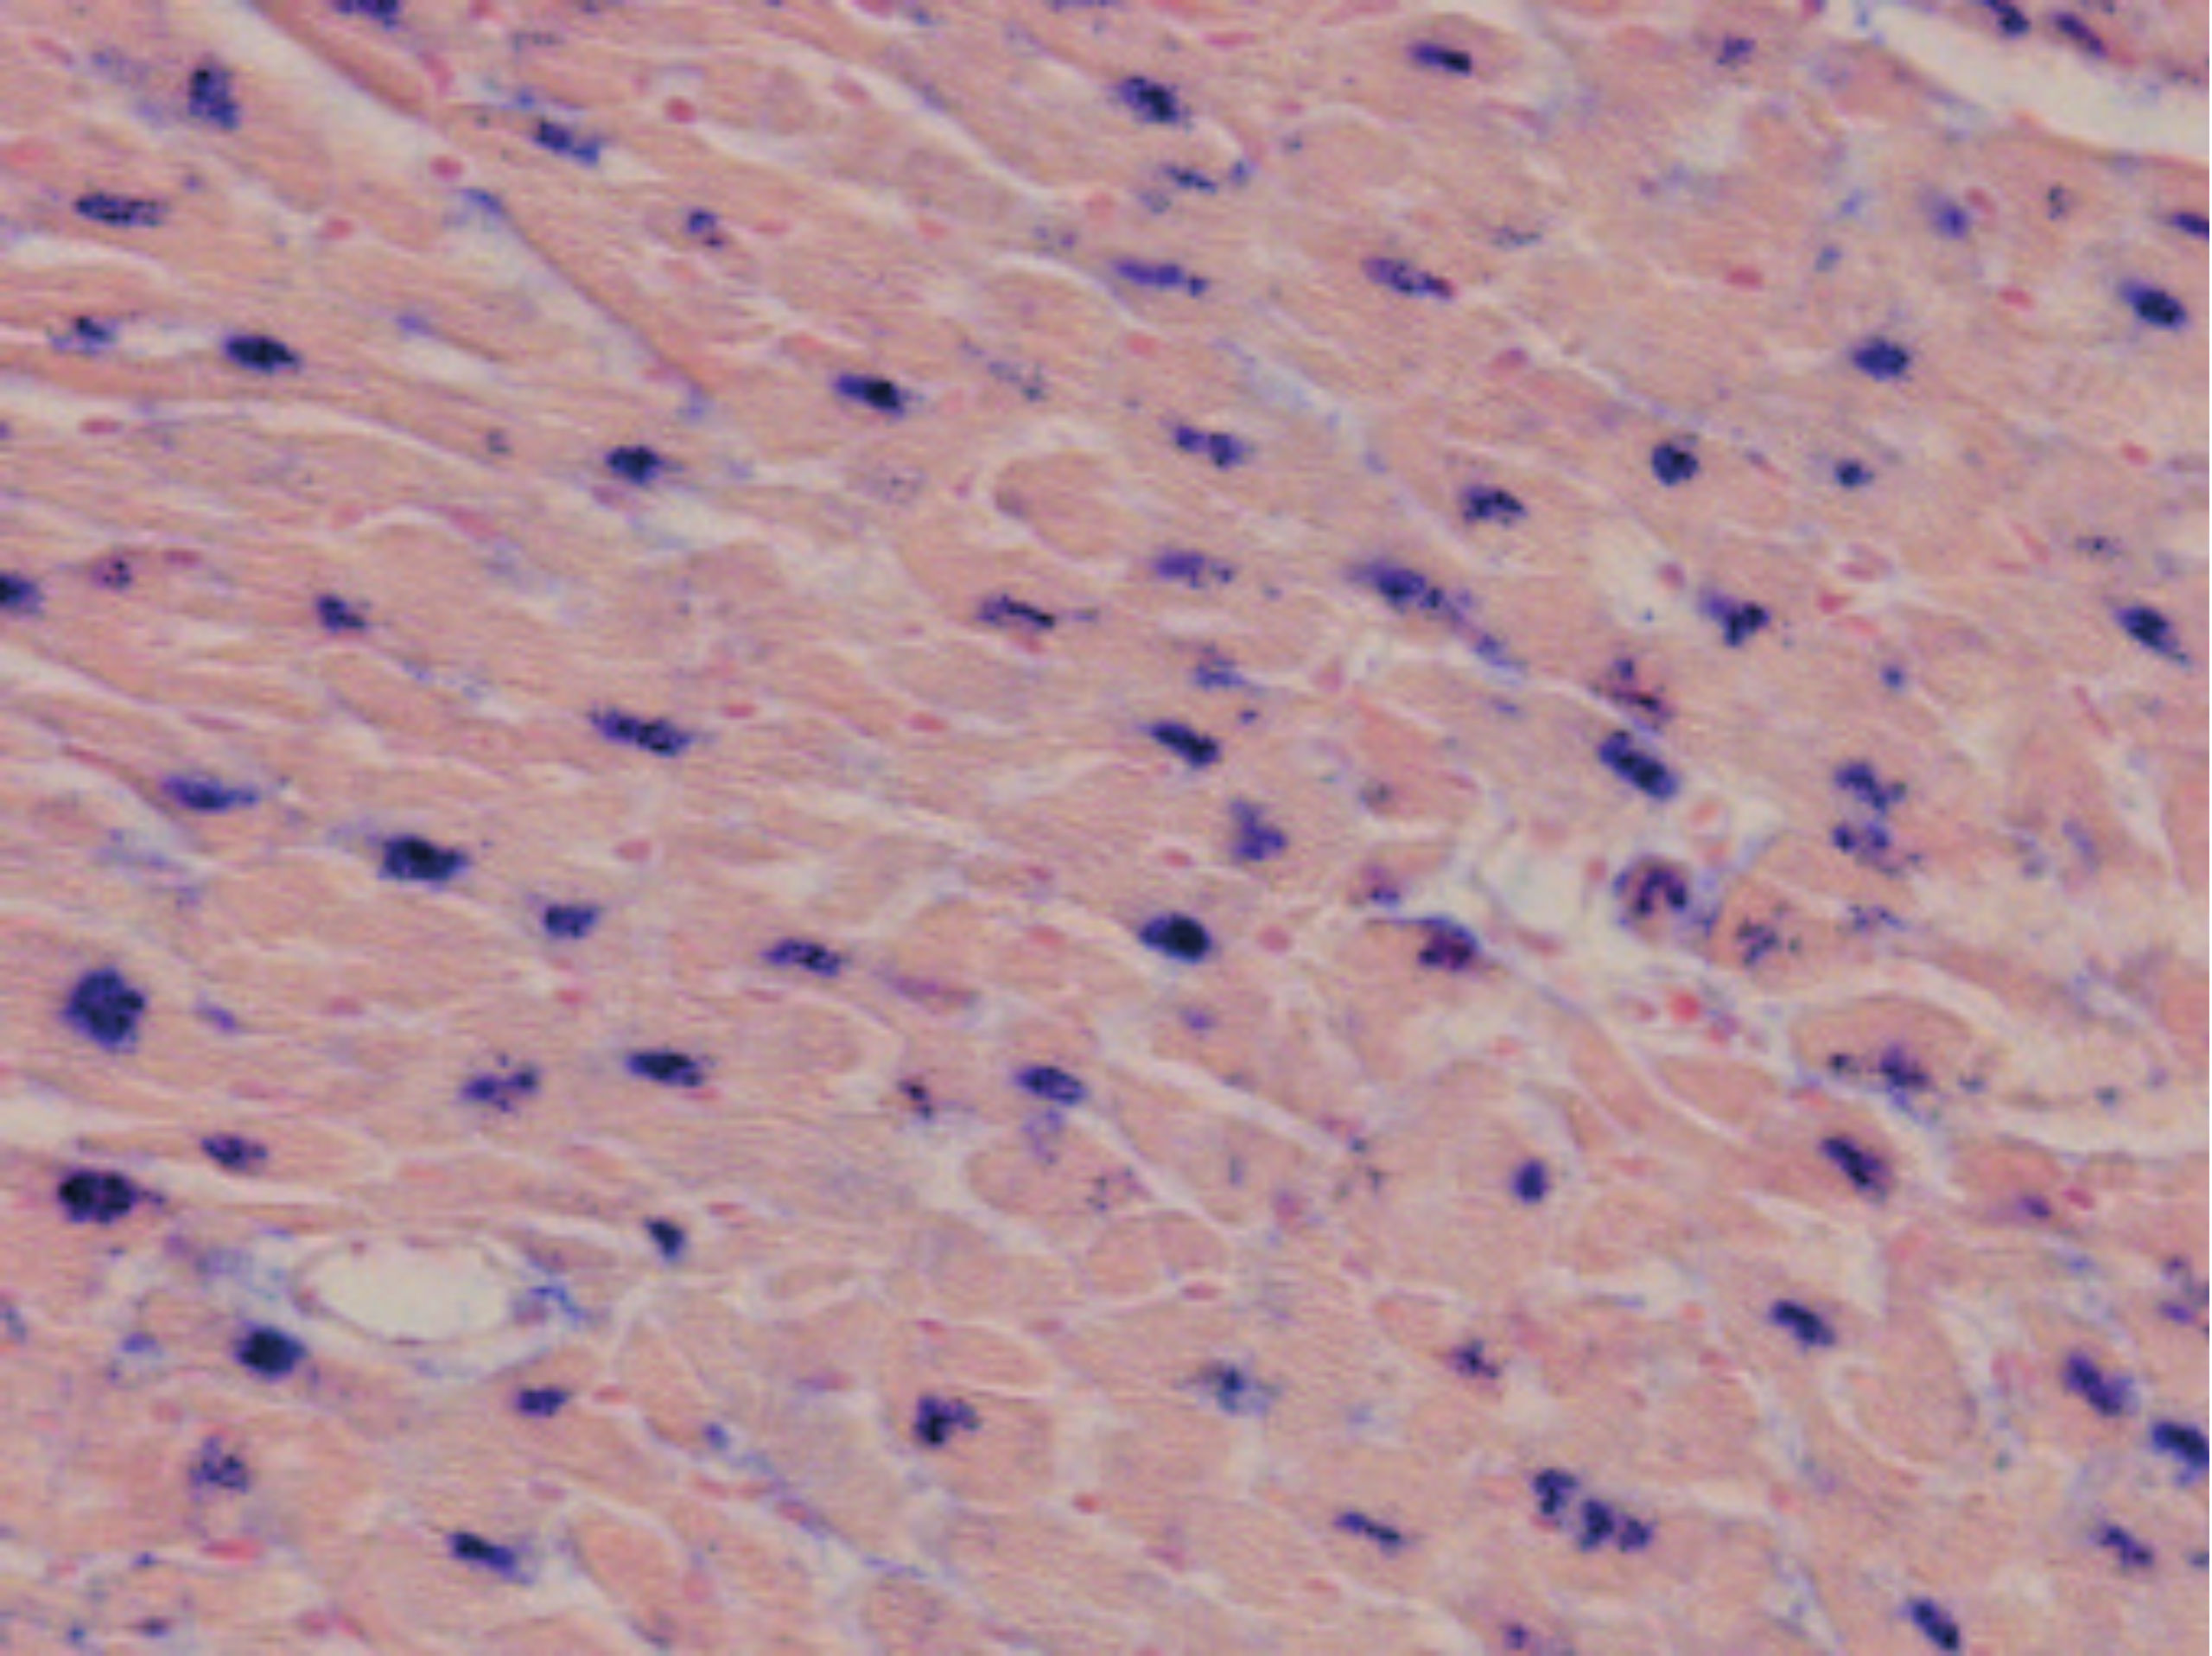

| Kit 1 | miR-1 | Skeletal muscle cells, myocytes, myocardiocytes | miR-1 detection in adult mouse heart |

| Kit 9 | miR-223 | Myeloid, granulocytic, and monocytic compartments of the hematopoietic system | miR-223 detection in esophagus cancer |